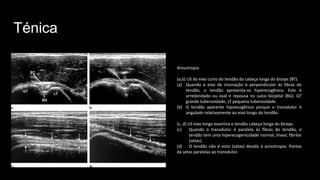

Anisotropia.

(a,b) US do eixo curto do tendão da cabeça longa do bíceps (BT).

(a) Quando o eixo de insonação é perpendicular às fibras do

tendão, o tendão apresenta-se hiperecogênico. Este é

arredondado ou oval e repousa no sulco bicipital (BG). GT

grande tuberosidade, LT pequena tuberosidade.

(b) O tendão aparente hipoecogênico porque o transdutor é

angulado relativamente ao eixo longo do tendão.

(c, d) US eixo longo examina o tendão cabeça longa do bíceps.

(c) Quando o transdutor é paralelo às fibras do tendão, o

tendão tem uma hiperecogenicidade normal, linear, fibrilar

(setas).

(d) O tendão não é visto (setas) devido à anisotropia. Pontas

da setas paralelas ao transdutor.